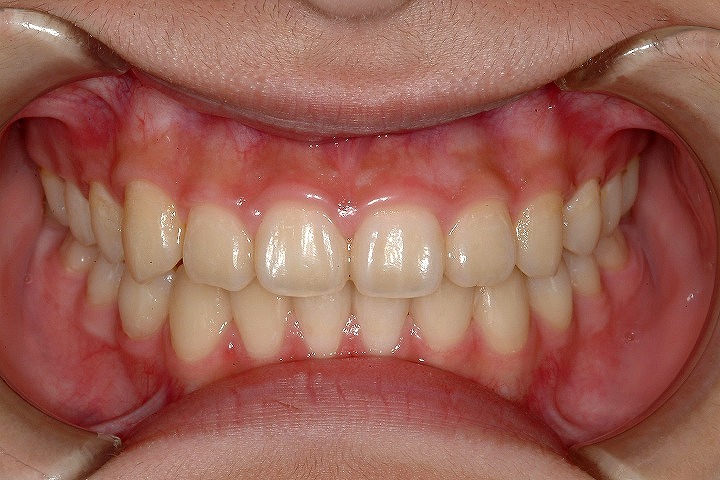

叢生(乱ぐい歯)

過蓋咬合(深いかみ合わせ)

歯のデコボコを主訴に来院された小学校5年生の患者さんです。叢生の程度は比較的重度でしたが、上顎第二大臼歯の萌出前であったので、ヘッドギアーとGMDを用い、大臼歯の後方への拡大を行いました。その後、その空隙を利用して、非抜歯でエッジワイズ装置を用いて配列を行いました。拡大処置1年6ヶ月、後期2年で治療いたしております。